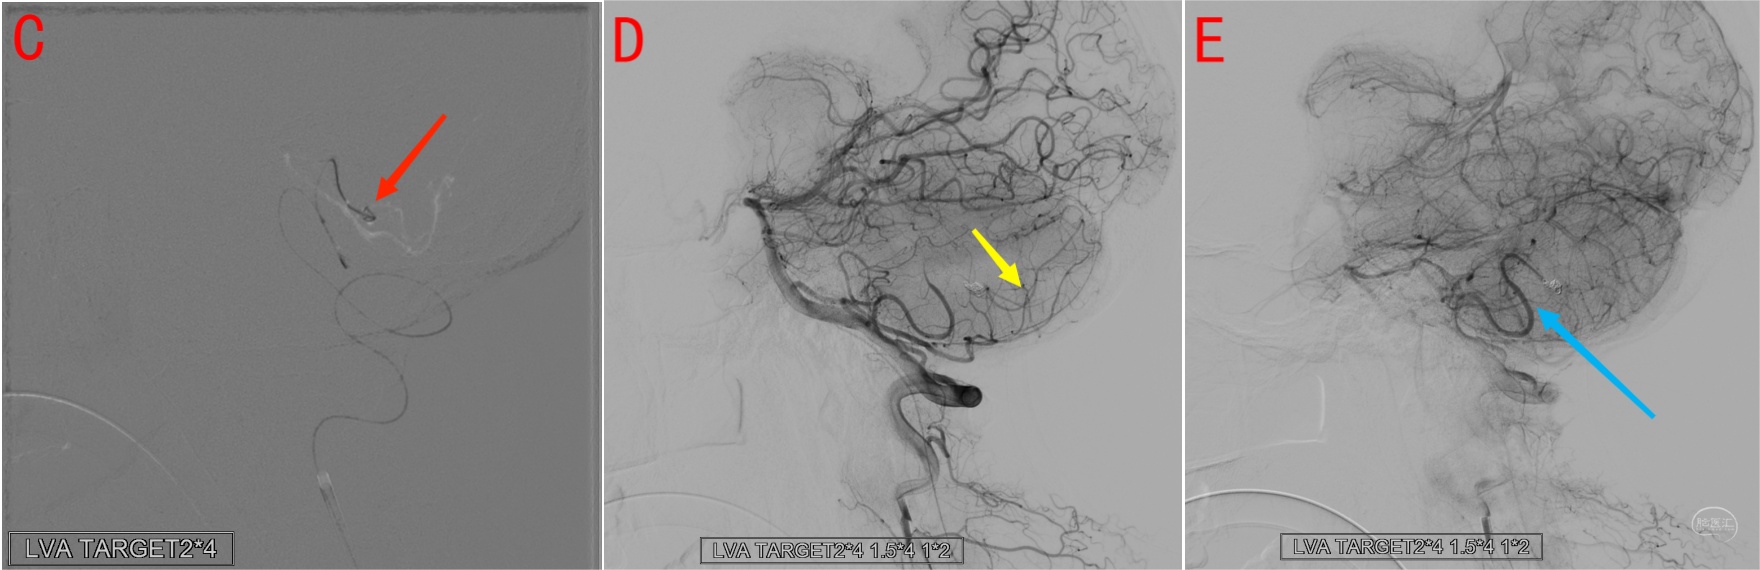

图12 小脑后下动脉远端动脉瘤。A为侧位造影,B为3D-MIP像,显示小脑后下动脉自椎动脉V3段发出,小脑后下动脉远端动脉瘤(黄箭)位于膜帆扁桃体段与皮层段交界区域。

图13 小脑后下动脉远端动脉瘤(同图12)栓塞及栓塞后造影。图C显示Headway DUO微导管进入动脉瘤内填塞弹簧圈(红箭),栓塞后造影显示动脉期小脑后下动脉皮层段(图D黄箭)经小脑前下动脉皮层支代偿显影;静脉期小脑后下动脉能够充盈至动脉瘤近端(图E 蓝箭),动脉瘤不显影。